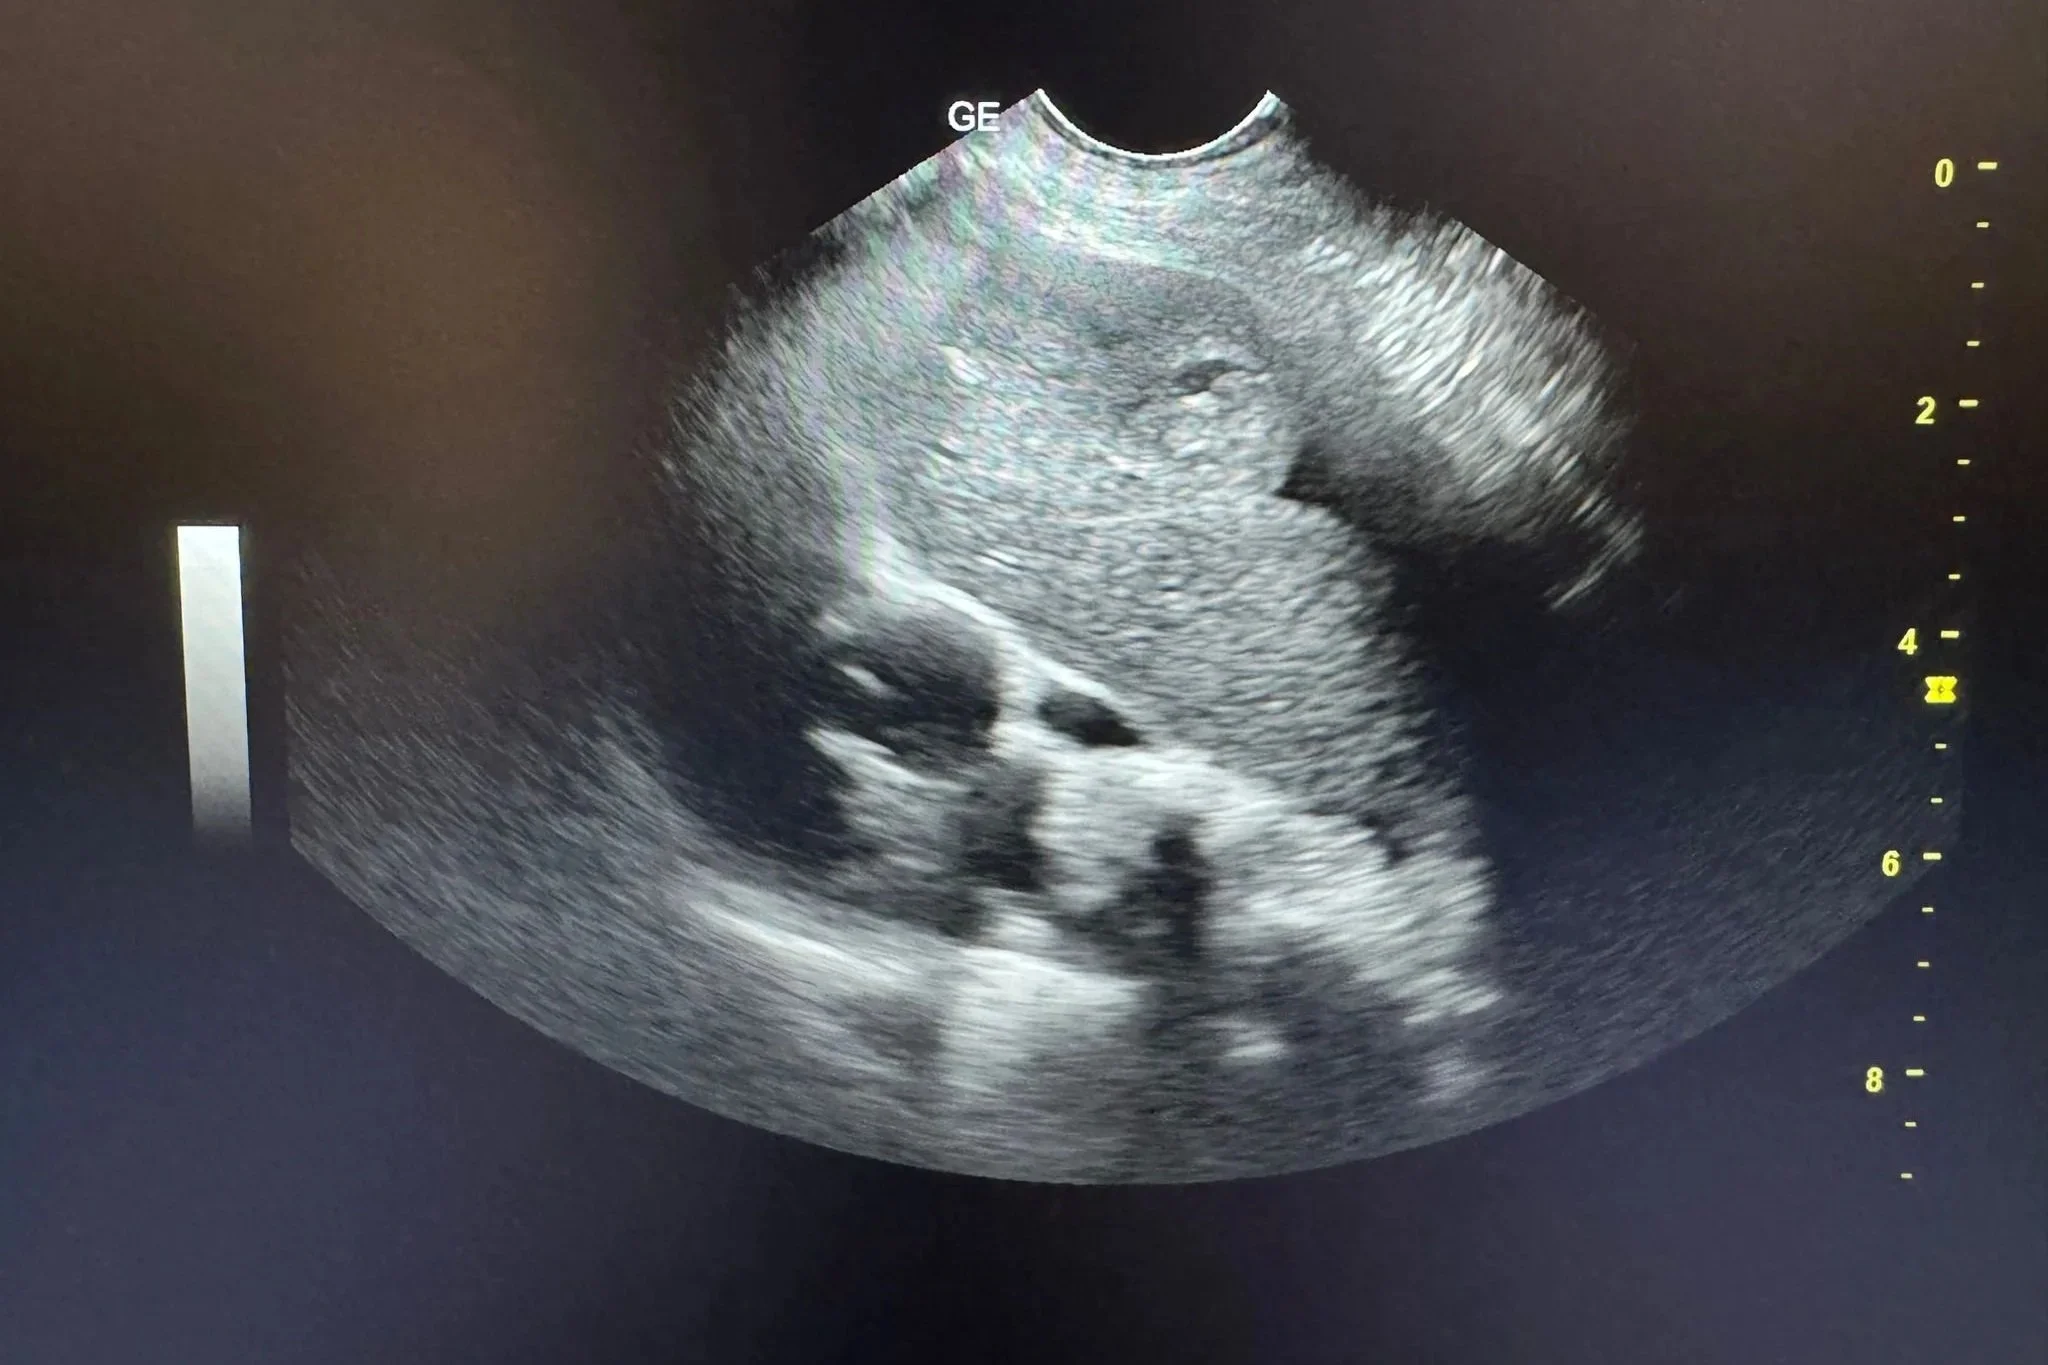

Ecografia toracică este o investigație imagistică neinvazivă care folosește ultrasunete pentru a evalua structurile din interiorul toracelui. Prin ecografie, medicul poate evalua în timp real plămânii, pleura, spațiul pleural, mediastinul, diafragma și, în anumite condiții, structurile cardiace. Procedura nu utilizează radiații ionizante, este nedureroasă și, în majoritatea cazurilor, nu necesită sedare.Pentru utilizare uzuală, ecografia toracică ajută la identificarea acumulărilor de lichid în jurul plămânilor, a modificărilor de țesut, a maselor sau a inflamațiilor. De exemplu, la o pisică care respiră dificil după un episod de stres, medicul poate depista rapid un revărsat pleural și poate decide pașii următori. La un câine în vârstă, ecografia poate oferi indicii despre o afecțiune cardiacă sau despre prezența unei formațiuni care necesită evaluări suplimentare.

Ecografia toracică se realizează în timp real, iar medicul observă imediat structurile examinate. Acest lucru permite ajustarea rapidă a investigației în funcție de ce apare pe ecran. De exemplu, dacă se observă lichid în cavitatea toracică, medicul poate evalua cantitatea și distribuția acestuia.Interpretarea rezultatelor ține cont de contextul clinic. O imagine ecografică nu se analizează izolat, ci în corelație cu simptomele, istoricul medical și alte teste efectuate. În unele cazuri, ecografia ridică suspiciuni care necesită confirmare prin analize de laborator sau prin alte metode imagistice. Pentru proprietari, este util de știut că medicul explică pe înțelesul lor ce a observat și ce înseamnă aceste descoperiri pentru sănătatea animalului. Întrebările sunt binevenite, iar clarificările ajută la înțelegerea pașilor următori.

Proprietarii întreabă adesea de ce medicul recomandă ecografie și nu radiografie sau invers. Fiecare metodă are indicații clare. Radiografia oferă o imagine statică, utilă pentru evaluarea structurii generale a toracelui. Ecografia, în schimb, permite observarea mișcărilor și a lichidelor în timp real. De exemplu, un revărsat pleural mic poate fi dificil de apreciat din punct de vedere radiologic, dar apare clar la ecografie. În schimb, leziunile profunde ale parenchimului pulmonar se văd mai bine radiologic. Medicul alege metoda care răspunde cel mai bine întrebării clinice, fără a expune inutil animalul la investigații suplimentare.